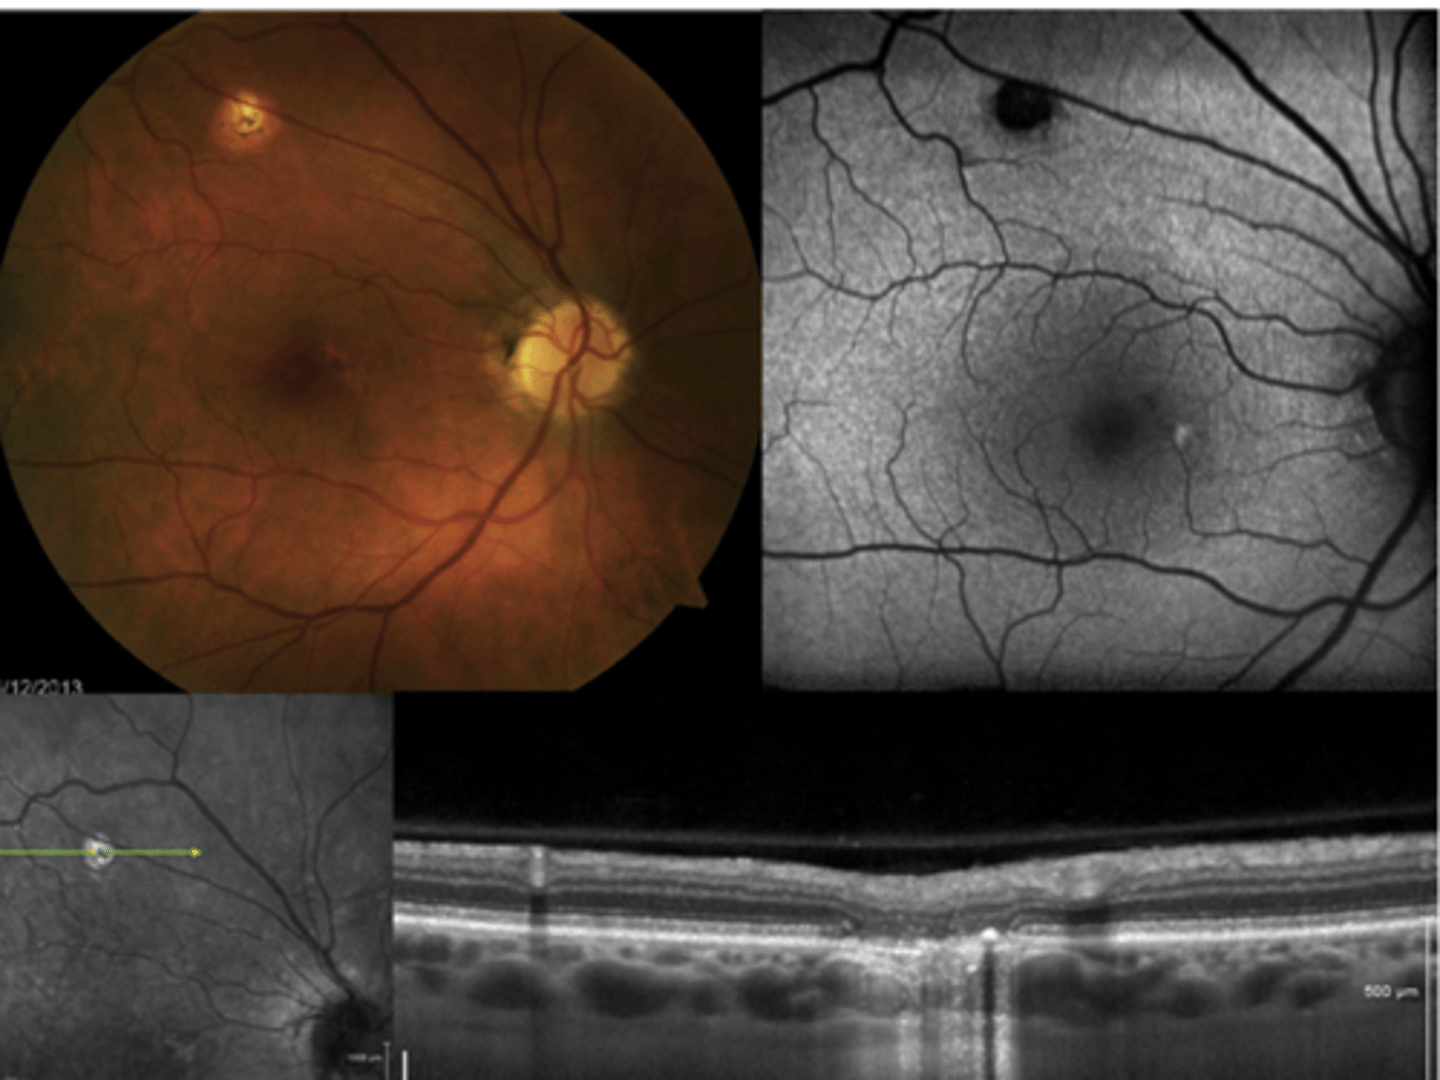

How does choroidal rupture appear on OCT here?

loss of RPE continuity at site of rupture = inner choroid atrophy

How does choroidal rupture appear on OCT here?

RPE disruption

+/- hemorrhage

How does choroidal rupture appear on FAF?

hypoAF where RPE is atrophied